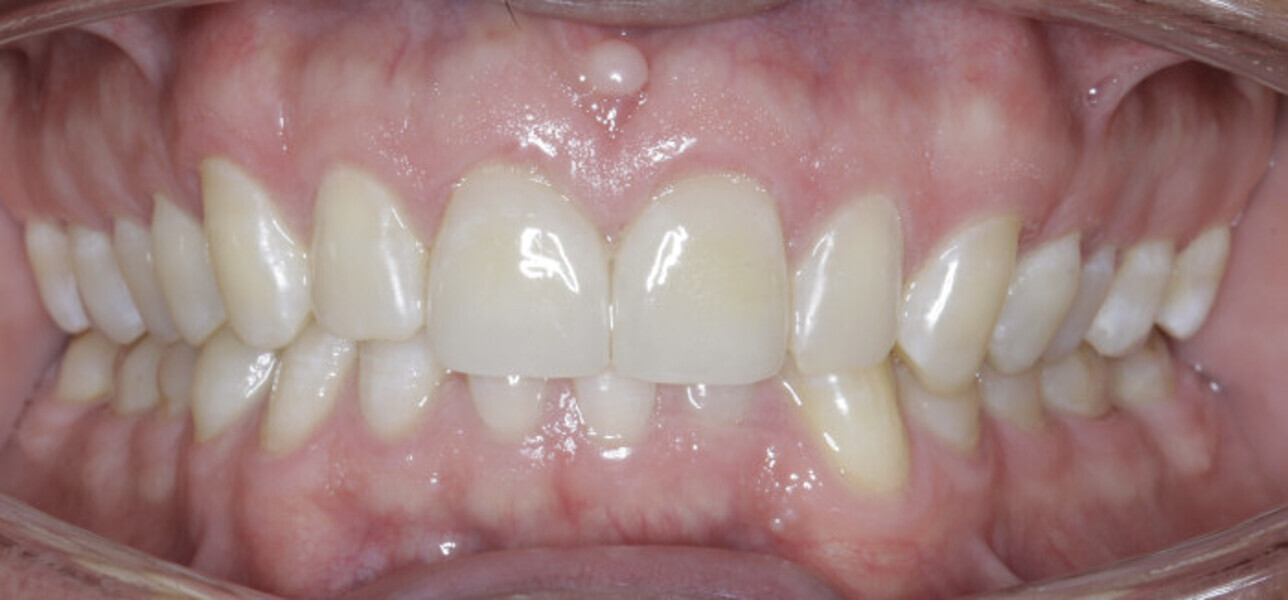

New Age orthodontics and orthopaedics with temporary anchorage devices